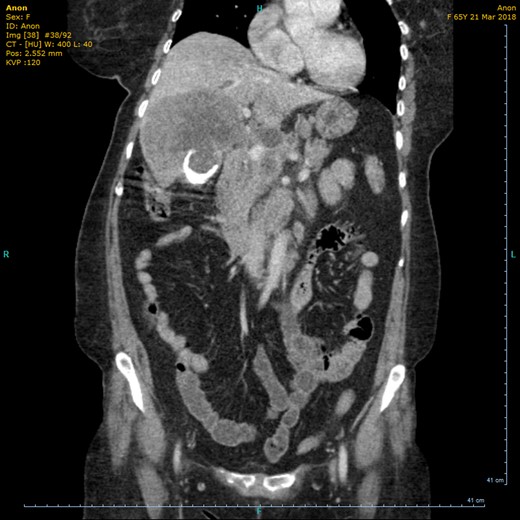

On the current admission, general examination was unremarkable and vital signs were normal. Abdominal examination revealed no organomegaly or palpable mass. Blood tests showed deranged liver function tests (ALT 45 U/l, ALP 775 U/l, total bilirubin 20umol/l, albumin 27 g/l, GGT 553 U/l), hypercalcaemia (adjusted calcium 2.73 mmol/l) and leukocytosis (WCC 10.8 × 109/l). US showed the gallbladder had poor delineation of the posterior wall and appeared large, solid and heterogenous with posterior dense shadowing and with calcific components. Where visualized, the CBD was of normal calibre and no intrahepatic duct dilatation was seen. There was a large, ill-defined heterogenous mass within the liver (Fig. 1). Subsequent computerized tomography (CT) showed a10cm solid porcelain gallbladder invading liver segments 4 and 5 (Fig. 2), with evidence of enlarged coeliac, peri-pancreatic and para-aortic lymph nodes as well as pulmonary metastatic deposits (T4 N1 M1).

CT (coronal view) showing circumferential calcification in the thickened wall of the gallbladder.